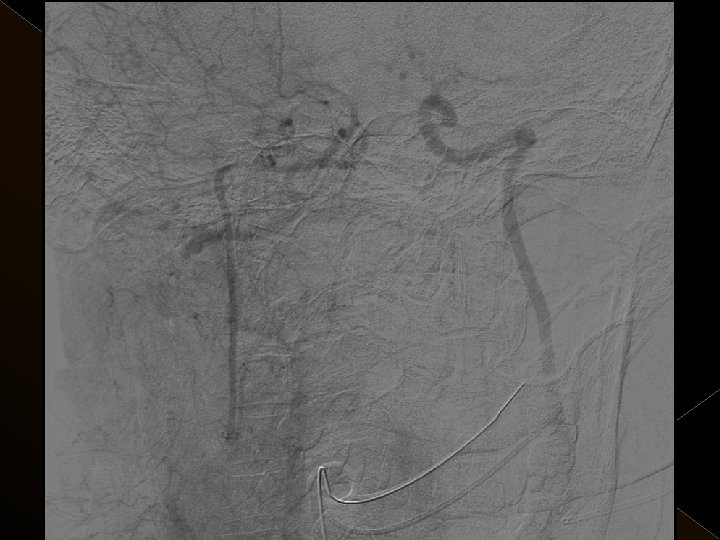

KOMPLİKASYONLAR Ponksiyon bölgesi komplikasyonları � Trombektomi stentine ait komplikasyon (*1) � Diseksiyon(*2) � Karotikokavernöz fistül (‘ 1) � Hemorajik komplikasyonlar(‘ 5) Semptomatik-nonsemptomatik � İskemik komplikasyonlar (3) � Reoklüzyon (2 i. a) � Kontrast madde nefropatisi �